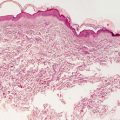

The histologic findings of acropustulosis of infancy are not specific, but characteristic of this entity. The epidermis has foci of spongiosis with microvesiculation [2] (Fig. 3.3). Neutrophilic abscesses are present within the vesicles (Fig. 3.4). Acute lesions do not have parakeratosis, although this is a common finding in more established lesions. Less commonly, eosinophils may be present within the microvesicles [3].

Fig. 3.3

Histologic features of acropustulosis of infancy include intraepidermal spongiosis and clusters of neutrophils within the stratum corneum